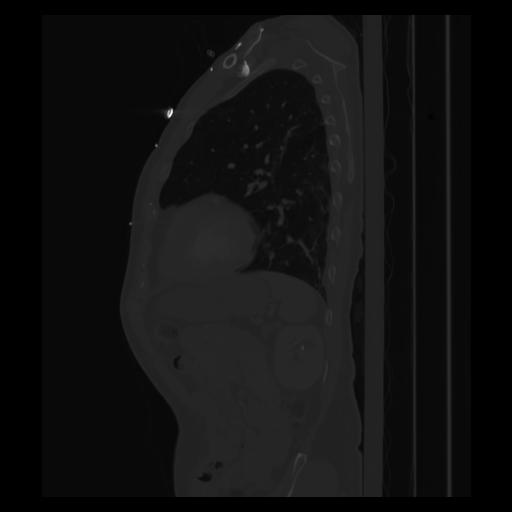

30 CUERPO,CE,Sagittal,3.000,CUERPO,Sagittal,